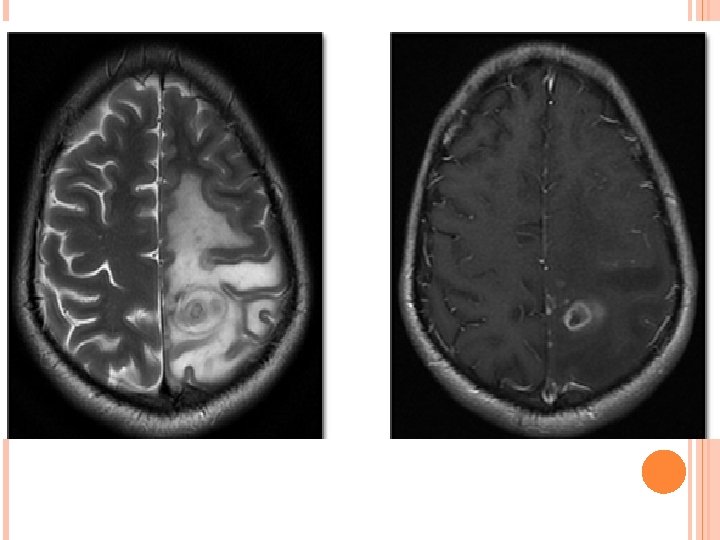

ENHANCING PARENCHYMAL LESIONS(TUBERCULOMA) Tuberculomas can be single or multiple and present anywhere in brain parenchyma. Usually conglomerated and coalesce to form non caseating granuloma, which further in most cases show central caseous necrosis and eventually liquefaction.

Depending on its stage of maturation tuberculoma’s appearance varies on MRI. Stages of tuberculoma: Non caseating Caseating with solid centre Caseating with liquid centre

NON CASEATING Hyperintense on. T 2 W images and slightly hypointense on T 1 W images with homogeneous post contrast enhancement.

CASEATING WITH SOLID CENTRE: Hypo to isointense on both T 1 W and T 2 W images with an iso to hyperintense rim on T 2 W images. In presence of an edema rim is inseparable on T 2 W images. Shows rim enhancement on post contrast T 1 W images.

0

CASEATING WITH LIQUID CENTRE: When the solid centre liquefies it appears hyperintense on T 2 W images with surrounding hypointensity. On post contrast images show rim enhancement.